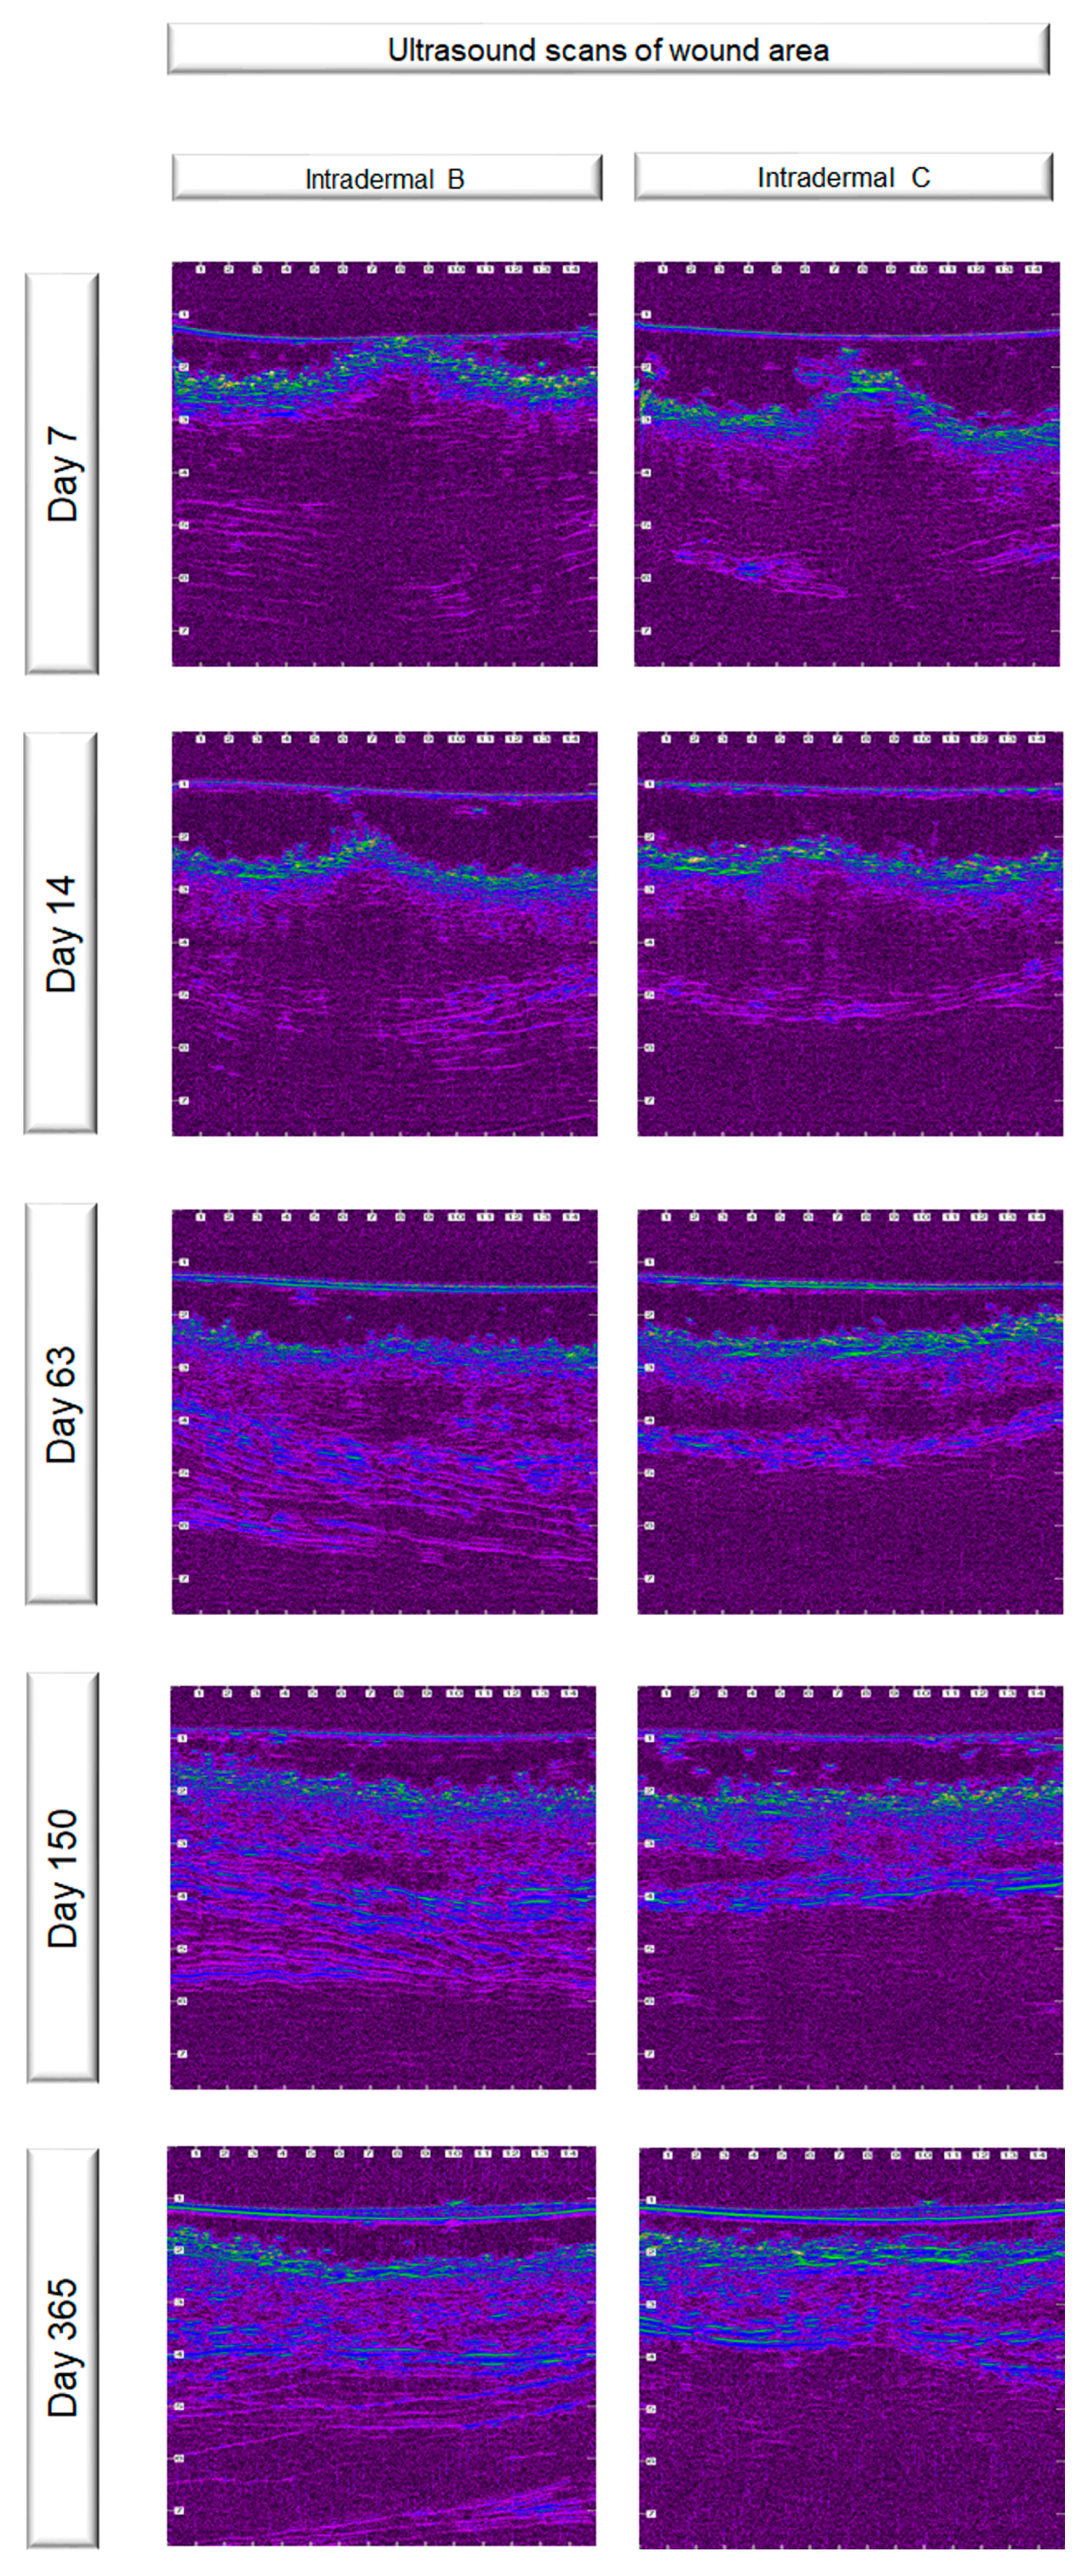

3.4. Ultrasonographic Evaluation

4.3. Ultrasonographic Evaluation

4.3.1. Ultrasonographic Findings